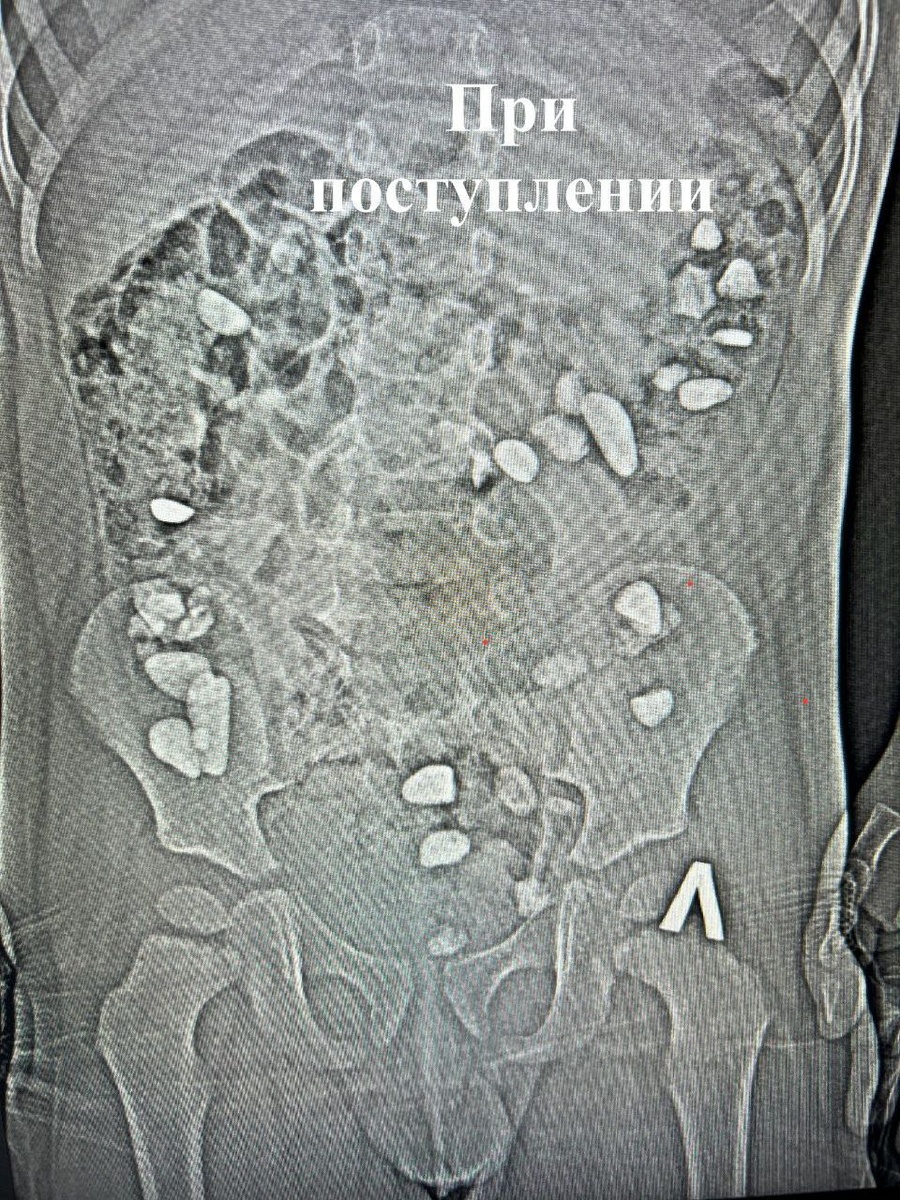

Трехлетний ребенок проглотил больше 25 камней в Ессентуках. Мальчика привезли в больницу с жалобами на боли и вздутие живота. Врачи сделали мальчику рентген и обнаружили в кишечнике камни.

К счастью, хирургическое вмешательство не потребовалось. Благодаря лечению камни вышли естественным путем. Маленькому пациенту провели очистительную и противовоспалительную терапию. Родители не смогли уточнить обстоятельства произошедшего.